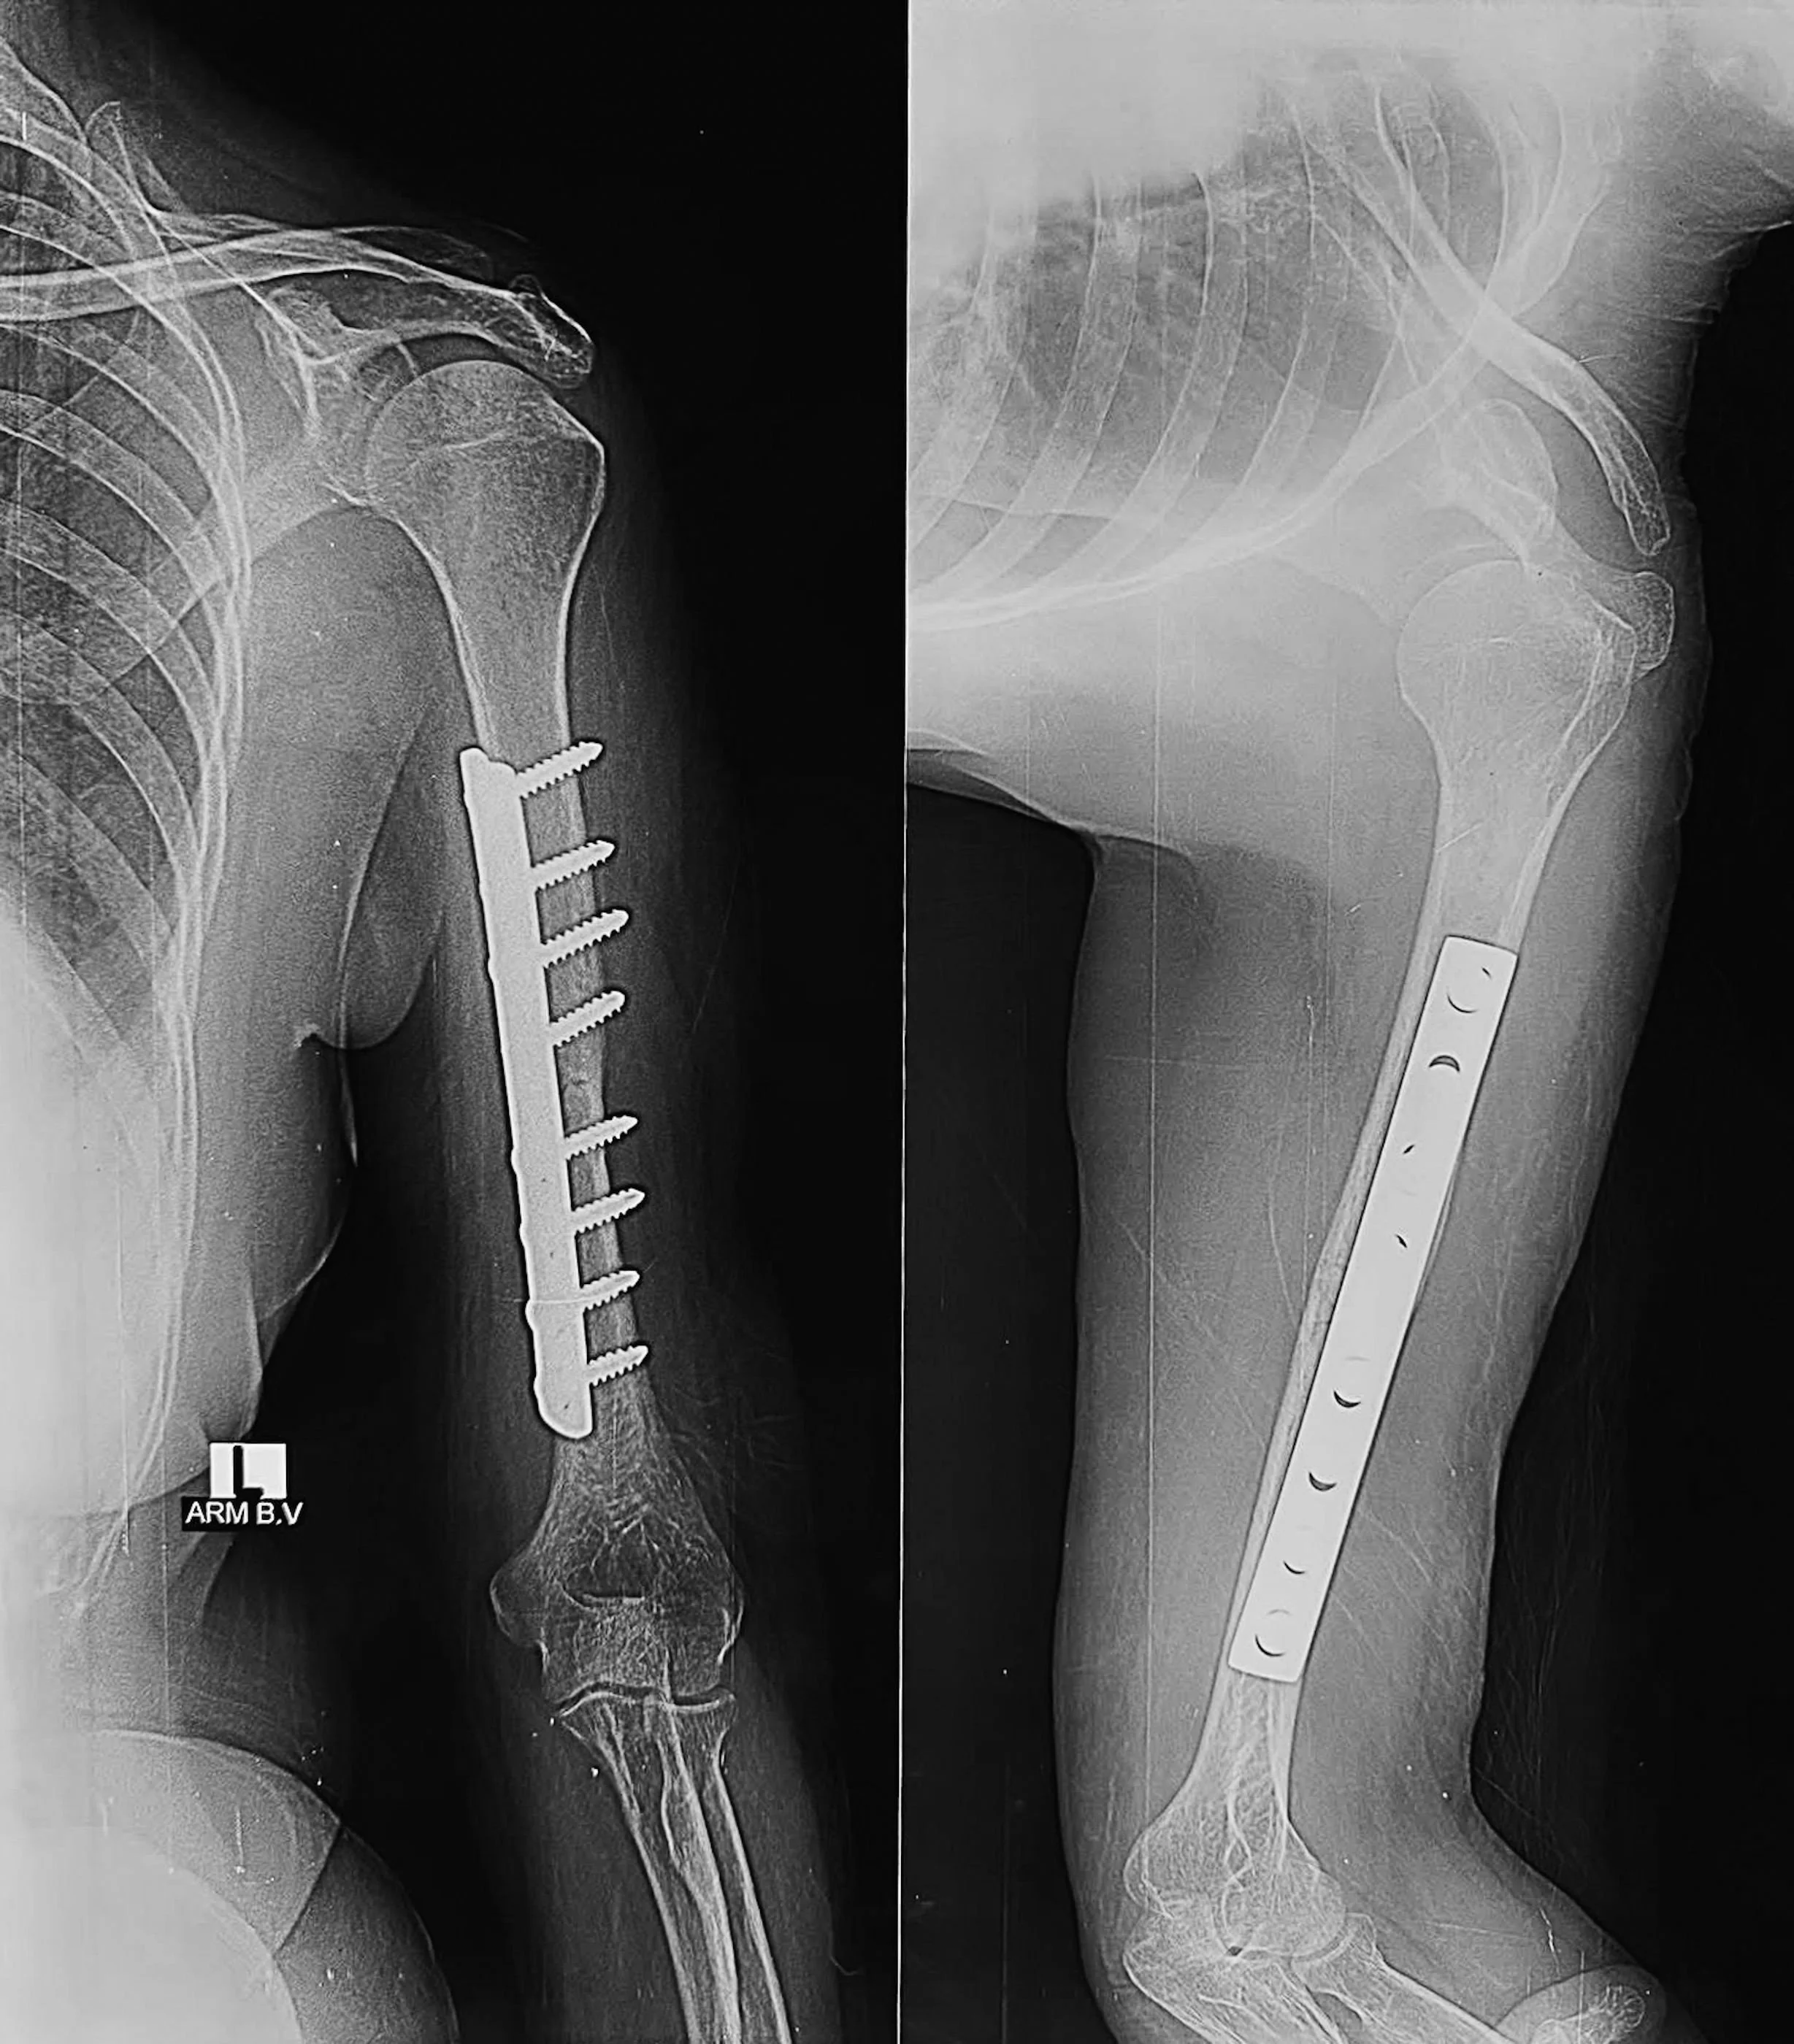

X-ray image showing a humerus with surgical plates and screws indicating a surgical repair of a fracture. - Dr. Kevin Wall, Richmond, VA

• Fixation: A long, contoured titanium or stainless steel plate is secured to the bone with multiple screws.